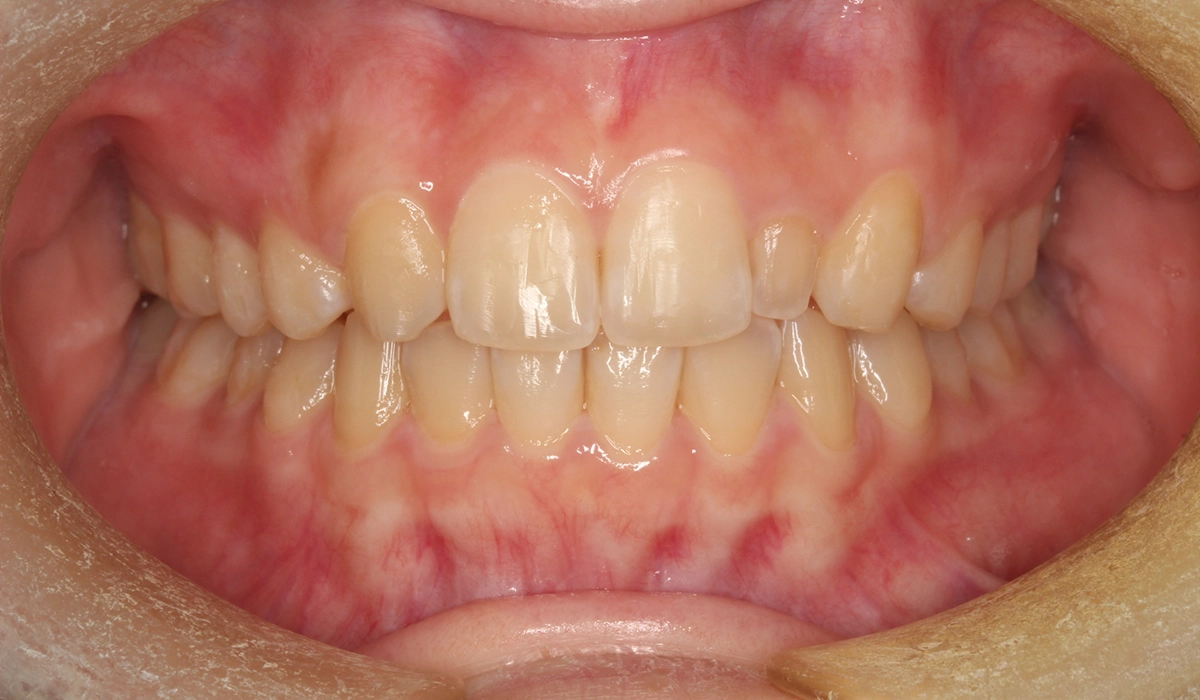

術後:正面

今回ご紹介する患者様は、上顎の歯並びのがたつきを気にされており、矯正検査後Ⅰ級叢生と診断いたしました。矮小歯があるため個性を生かして配列。

| 治療内容 | 上顎の歯並びのがたつきを気にされており、矯正検査後Ⅰ級叢生と診断。矮小歯があるため個性を生かして配列。 |